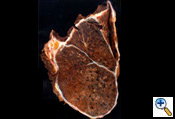

After completion of the en bloc dissection, 250 mg of SoluCortef is given intravenously. After approximately 10 minutes, the right pulmonary artery, superior and inferior pulmonary veins are ligated and divided with endoscopic 45 mm vascular staples intrapericardially (Figure 7). After the vessels are divided, the pericardium is opened posteriorly to the hilum, which completes the pericardial resection. The surgical specimen is then retracted anteriorly. The right mainstem bronchus is dissected free of peribronchial tissue and stapled with a 30 mm heavy wire stapler. The specimen (Figure 9) is removed and sent to the pathologist for inspection of resection margins, lymph node evaluation, and histological identification of the tumor. An intraoperative picture after removal of the en bloc specimen containing the lung, parietal pleura, pericardium and diaphragm is shown in (Figure 10).